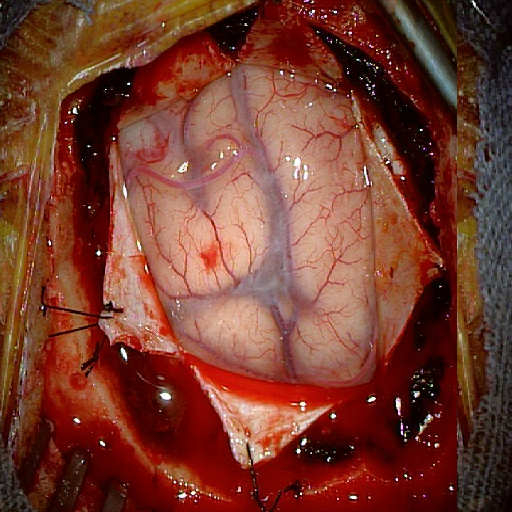

We tested our method retrospectively on 6 clinical datasets from 6 patients (cases) (see Fig. 5). These consisted of preoperative T1 contrast MRI scans and intraoperative images of the brain surface after dura opening. Cortical vessels around the tumors were segmented and triangulated to generate 3D meshes using 3D Slicer. We generated 100 poses for each 3D mesh (i.e.: each case) and used a total of 15 unique textures from human brain surfaces (different from our 6 clinical datasets) for synthesis using . In order to account for potential intraoperative brain deformations [4] we augment the textured projection with elastic deformation [21] resulting in approximately 1500 images per case. The surgical images of the brain (left image of the stereoscopic camera) were acquired with a Carl Zeiss surgical microscope. The ground-truth poses were obtained by manually aligning the 3D meshes on their corresponding images.

Fig. 5 shows our results as Augmented Reality views with bounding boxes and overlaid meshes. Our method produced visually consistent alignments for all 6 clinical cases without the need for initial registration. Because our current method does not account for brain-shift deformation, our method produced some misalignment errors. However, in all cases, our predictions are similar to the ground truth.